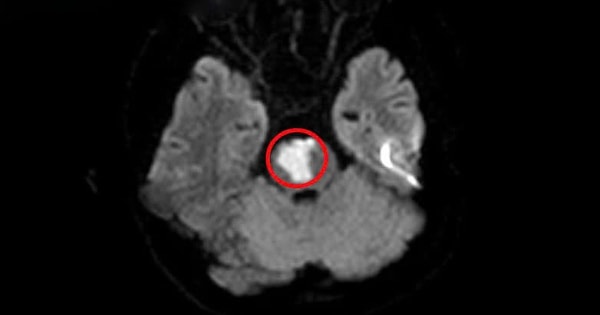

Bệnh nhân 17 tuổi bị nhồi máu não, thừa nhận phạm sai lầm nhiều người Việt dễ mắc phải

Bệnh nhân 17 tuổi bị đau đầu, chóng mặt tự mua thuốc về uống nhưng không khỏi, đến khi nhập viện phát hiện bị nhồi máu não.